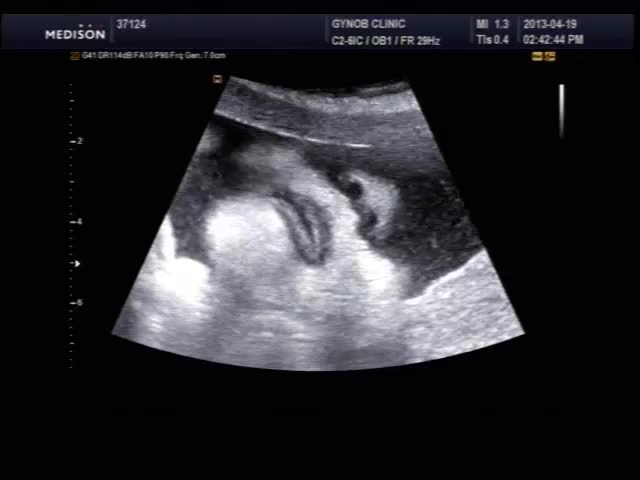

오늘 초음파 보신 산모의 영상인데 태아의 입과 인중 부분이 잘 보이는 편이라 여러분들께 보여드릴 겸, 그리고 설명 드릴 것도 있고 해서 올려 봅니다.

초음파 검사시 태아의 입과 인중을 살펴보는 것은 구순열과 같은 기형이 있는가 보는 목적이며 요즘은 초음파 장비 기술이 발달하여 비교적 쉽게 중기에 진단이 가능합니다.

태아는 뱃속에서도 보고 듣고 먹고 다 할 수 있는데 위 영상을 보시면 태아가 입을 오물거리면서 무언가를 말하는 것도 같지만 사실 말을 하는 것은 아니고 음식을 먹는 운동을 하면서 실제 양수를 삼키는 모습입니다.

mouth.mp4.jpg (19.94 KB, 다운수: 478)

mouth.mp4.jpg

몇주나 되면 저렇게 뚜렷한 얼굴 형태가 보이나요..??!!!

뻐끔거리는 입도 잘 보이고 콧구멍도 잘보이고~~ 완전 신기하네요~~!! ^0^

24주 이상되면 다 저런 모습으로 볼 수 있습니다. 물론 아기 자세가 받쳐주어야 하지만....  등록시간 2013-04-19 19:01